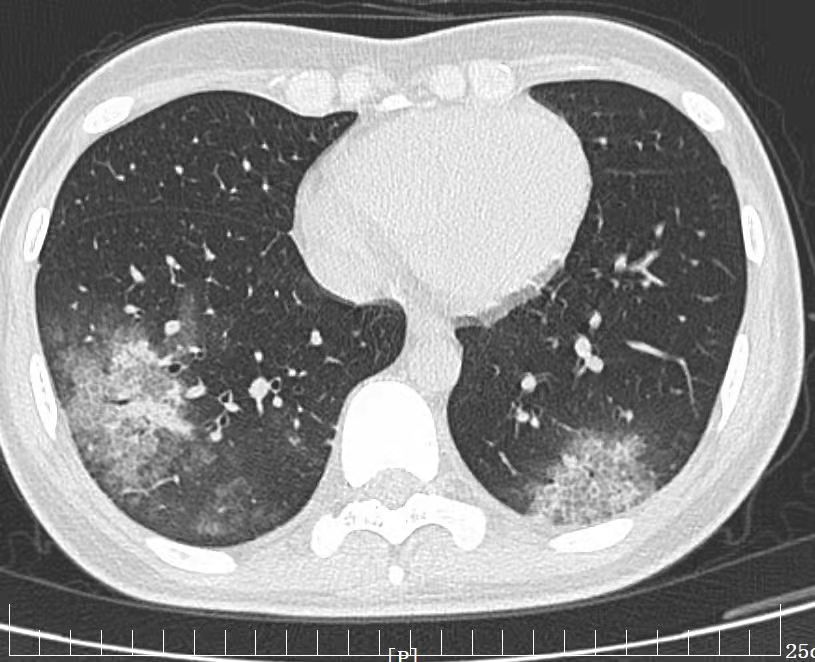

張女士,今年26歲,既往身體健康,近日出現(xiàn)咳嗽、胸悶、發(fā)熱,在家口服藥無(wú)效,遂就診于西安高新醫(yī)院呼吸與危重癥醫(yī)學(xué)科,行胸部CT檢查發(fā)現(xiàn)肺部多發(fā)“團(tuán)片影”。主管醫(yī)生李霞發(fā)現(xiàn)其肺部病灶與普通肺炎影像表現(xiàn)不一,感染病原微生物到底是什么?

經(jīng)上級(jí)醫(yī)師高和飛副主任醫(yī)師仔細(xì)閱讀患者胸部CT,發(fā)現(xiàn)其肺部病灶的確“不典型”,經(jīng)仔細(xì)追問患者接觸史,了解到張女士特別喜歡鳥,這幾年在家養(yǎng)了一只美麗的鸚鵡,可愛的鸚鵡讓她愛不釋手,且經(jīng)常密切接觸。考慮患者肺炎不排除與鸚鵡接觸有關(guān),高和飛副主任醫(yī)師及時(shí)給予其行支氣管鏡檢查,經(jīng)支氣管鏡下收集肺灌洗液行mNGS(病原微生物宏基因組檢測(cè))檢測(cè)出鸚鵡熱衣原體,最后確定此次導(dǎo)致“不典型肺炎”的真正“殺手”是比較罕見的鸚鵡熱衣原體所致。經(jīng)及時(shí)調(diào)整抗生素治療患者痊愈出院。